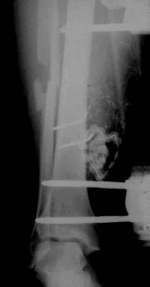

| Die offene Unterschenkelfraktur wird mit dem dynamischen Fixateur

Monotube versorgt. Durch die zusätzliche Fixierung mit Drähten

ist die Faktur nicht dynamisch stabilisiert. Trotz primärer Frakturheilung

und baldiger Belastung ist keine Knochenbildung zu erkennen. |